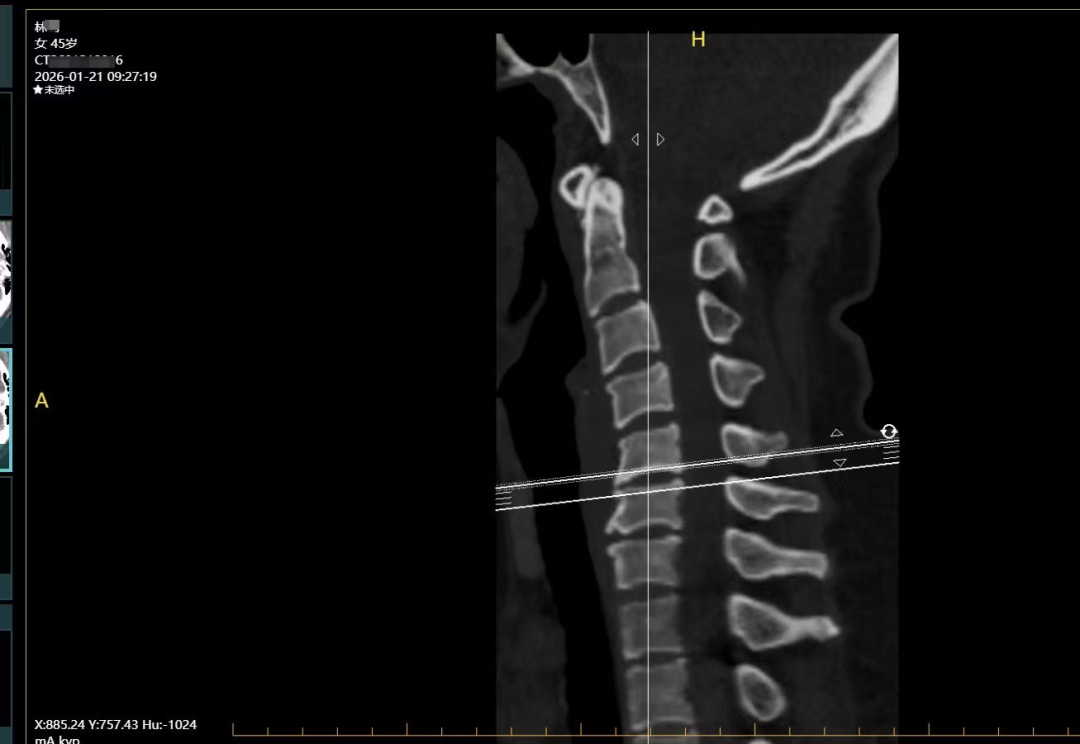

西医诊断: 颈椎间盘突出症(C4/5)

按语:本案患者为45岁女性,以左颈肩部及左手臂酸痛20余天为主诉就诊,结合查体、CT辅助检查,三步定位诊断颈椎间盘突出症(C4/5)诊断明确。由于患者是一位慢性肾脏病3期,同时兼有多种慢性疾病基础,所以在治疗方案首选非药物针刺为佳。